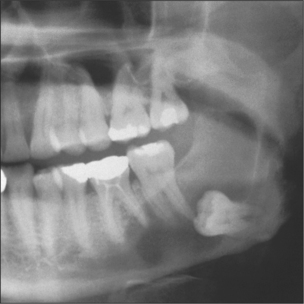

Radicular (dental) cysts are the most common of all cysts and are associated with a non-vital root of a tooth. Ectopic teeth can often be associated with cysts either as the primary cause as with the dentigerous cyst (Fig. 9.2) or when displaced by a cyst, such as an odontogenic keratocyst. It is important to appreciate that other more significant conditions, e.g. ameloblastoma, may also present in this manner (see Ch. 8).

Fig. 9.2 A dentigerous cyst associated with an unerupted lower third molar.